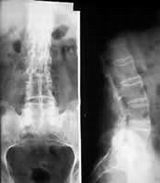

强直性脊柱炎是一种发生在腰、颈、胸段脊柱关节、韧带以及骶髂关节的炎症和骨化的病变,从开始的间歇性疼痛到持续性,再到脊柱由下而上强直,病情不断发展髋关节也会受累,从而发生股骨头坏死。

强直性脊柱炎造成股骨头坏死是一种病理的改变,强直性脊柱炎发病后会不断侵袭骶髂关节和脊柱,在此同时也会侵犯髋关节的滑膜,使髋关节滑膜萎缩或消失,这时髋臼和股骨头的表面软骨失去了髋关节滑膜的营养,出现软骨营养障碍,使软骨下骨细胞坏死,由此引发髋臼及股骨头软骨面蜂窝样的改变,髋臼及股骨头软骨面粗糙,髋关节在活动时摩擦力增大,易发生髋关节疼痛;或是因为髋臼外缘周围的韧带固化,形成退行性骨质增生,而在组成髋关节时股骨头深嵌在髋臼中,髋臼包绕股骨头近2/3,当髋臼发生异常,就会引发髋关节功能障碍,久而久之形成股骨头坏死。>>>您是否已经出现颈椎疼痛等症状?您是否是患上了强直性脊柱炎?点击免费咨询专家